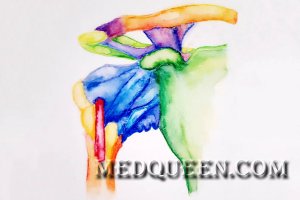

Плечевой суставПлечевой сустав (articulatio humeri; или лопаточно-плечевой сустав) – шаровидное соединение головки плечевой кости и суставной впадиной лопатки. Капсулу плечевого сустава окружают подакромиальная сумка и вращающая манжета, включающая сухожилия круглой, подлопаточной, надостной и подостной мышц. Плечевой пояс образован лопатками и ключицами, которые объединены ключично-акромиальным суставом.

Плечевой суставПлечевой сустав (articulatio humeri; или лопаточно-плечевой сустав) – шаровидное соединение головки плечевой кости и суставной впадиной лопатки. Капсулу плечевого сустава окружают подакромиальная сумка и вращающая манжета, включающая сухожилия круглой, подлопаточной, надостной и подостной мышц. Плечевой пояс образован лопатками и ключицами, которые объединены ключично-акромиальным суставом.

Плечевой сустав за счет своего строения позволяет выполнять разные движения: вращение (ротацию), сгибание, разгибание, отведение, приведение. Отметим, что истинный объем движения в плечевом суставе обусловлен углом движения без участия лопатки, а полный объем – с участием. Отведение плеча до уровня 90° (горизонтального уровня) осуществляется сначала путем сокращения musculus supraspinatus (надостной мышцы) (до уровня от 0 до 30°), потом musculus deltoideus (дельтовидной мышцы). Отведение плеча более 90° (выше горизонтальной линии) сопровождается вращением лопатки за счет сокращения musculus trapezius (трапециевидной мышцы).

Приведение плеча осуществляется musculus pectoralis major и musculus latissimus dorsi (большой грудной мышцей и широчайшей мышцей спины), сгибание вперед – musculus pectoralis major и передними волокнами musculus deltoideus (дельтовидной мышцы); разгибание – musculus latissimus dorsi, musculus teres major (большой круглой мышцей) и задними волокнами musculus deltoideus.

Супинация (наружная ротация) осуществляется путем сокращения подостной мышцы, пронация (внутренняя ротация) – передними волокнами дельтовидной, большой грудной мышцами и широчайшей мышцей спины.